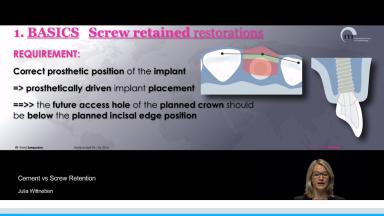

The lecture describes treatment planning for screw-retained and cemented prostheses and includes clinical cases related to each procedure. Advantages and disadvantages of screw- and cement-retained prostheses are given, including indications for each. Specific aspects of single-tooth implant prostheses, implant fixed dental prostheses (FDP), and full-arch prostheses are presented.

- plan implant positioning according to the intended type of prosthesis retention

- design prostheses for screw-retained and/or cement-retained implant situations